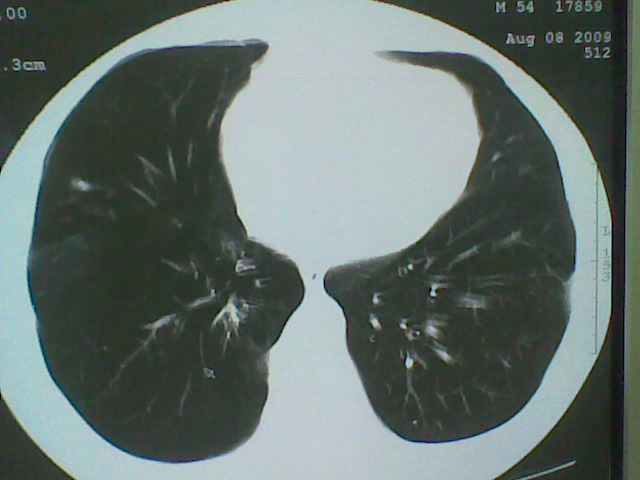

标题: CT21512:支扩伴感染?

患者女。咳嗽数天,咯血半天。

我们报的是支扩伴感染?

支持 支气管扩张并感染。

支持楼主意见,考虑支气管扩张并感染。

支气管扩张并感染。

支持楼主意见,还有肺气肿